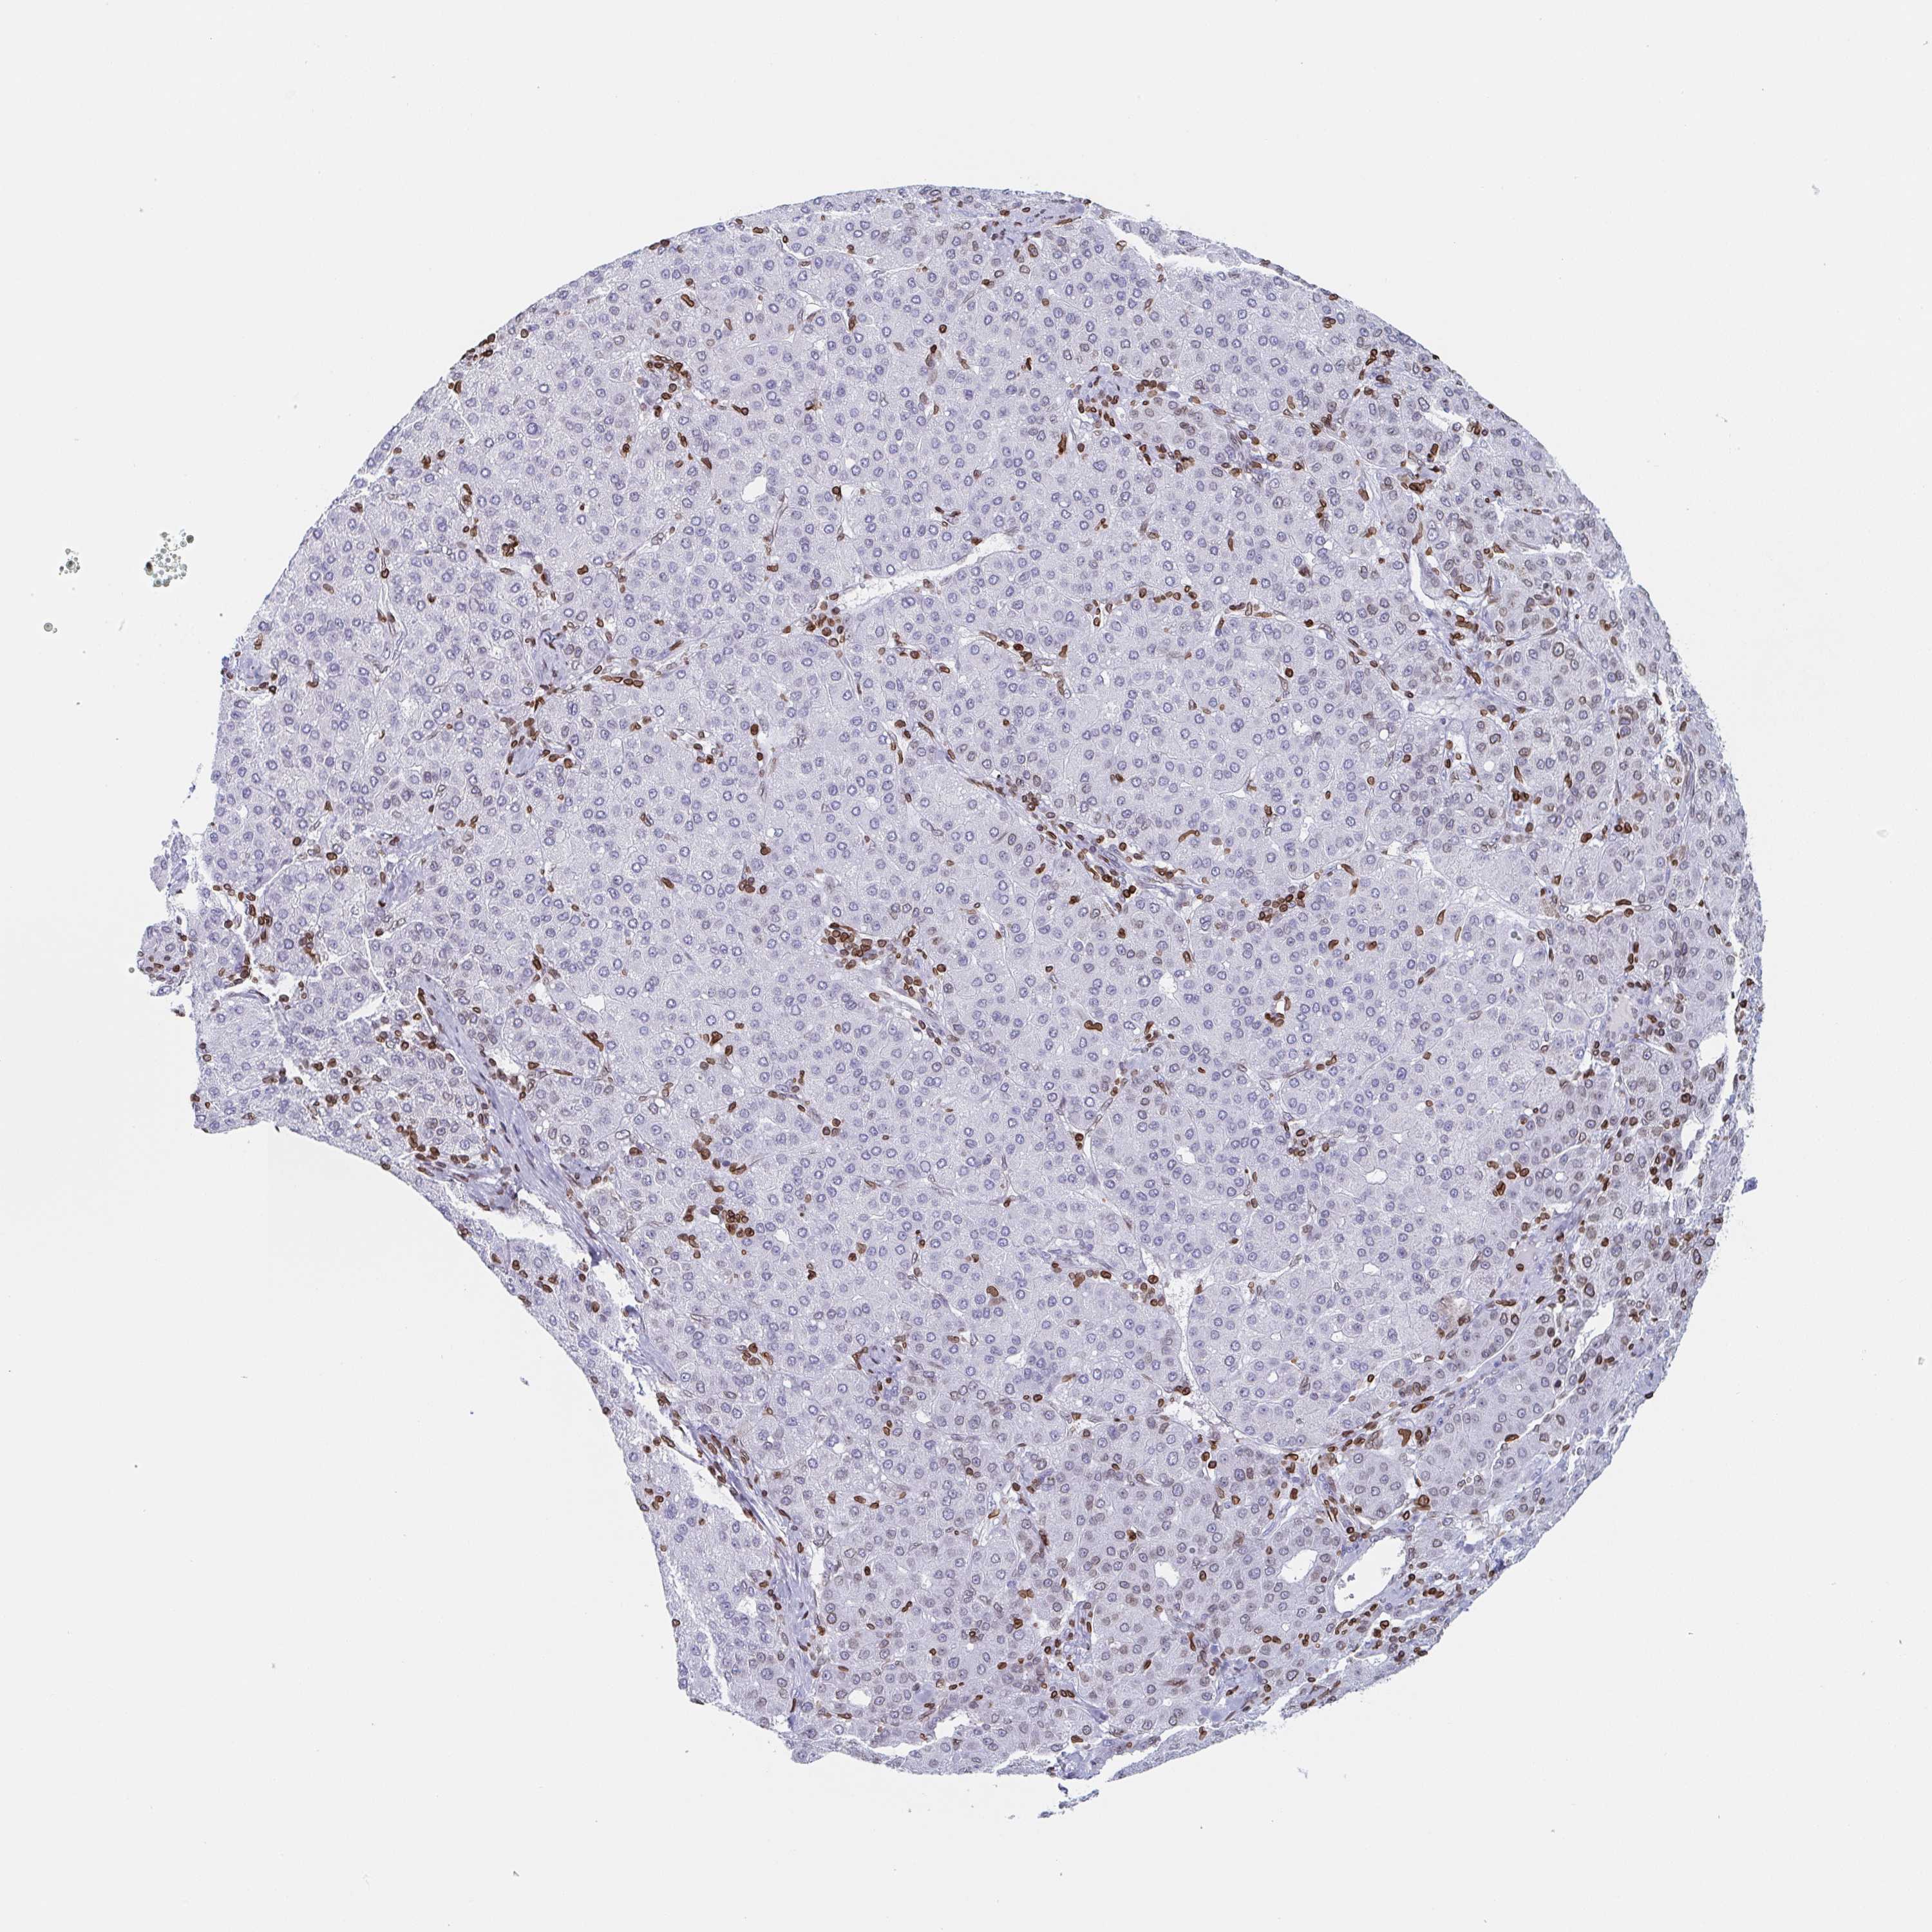

LIVER CANCER - Protein expressioni

A mouse-over function shows sample information and annotation data. Click on an image to view it in a full screen mode. Samples can be filtered based on level of antibody staining by selecting one or several of the following categories: high, medium, low and not detected. The assay and annotation is described here.

Note that samples used for immunohistochemistry by the Human Protein Atlas do not correspond to samples in the TCGA dataset.

Antibody stainingi

Antibody staining in the annotated cell types in the current human tissue is reported as not detected, low, medium, or high, based on conventional immunohistochemistry profiling in selected tissues. This score is based on the combination of the staining intensity and fraction of stained cells.

Each image is clickable and will lead to virtual microscopy that enables deeper exploration of all samples and also displays staining intensity scores, fraction scores and subcellular localization as well as patient and tissue information for each sample.

Antibody HPA049926

Antibody HPA053406

Staining

High

Medium

Low

Not detected

Intensity

Strong

Moderate

Weak

Negative

Quantity

>75%

75%-25%

<25%

None

Location

Nuclear

Cytoplasmic/membranous

Cytoplasmic/membranous,nuclear

Cholangiocarcinoma

Carcinoma, Hepatocellular, NOS